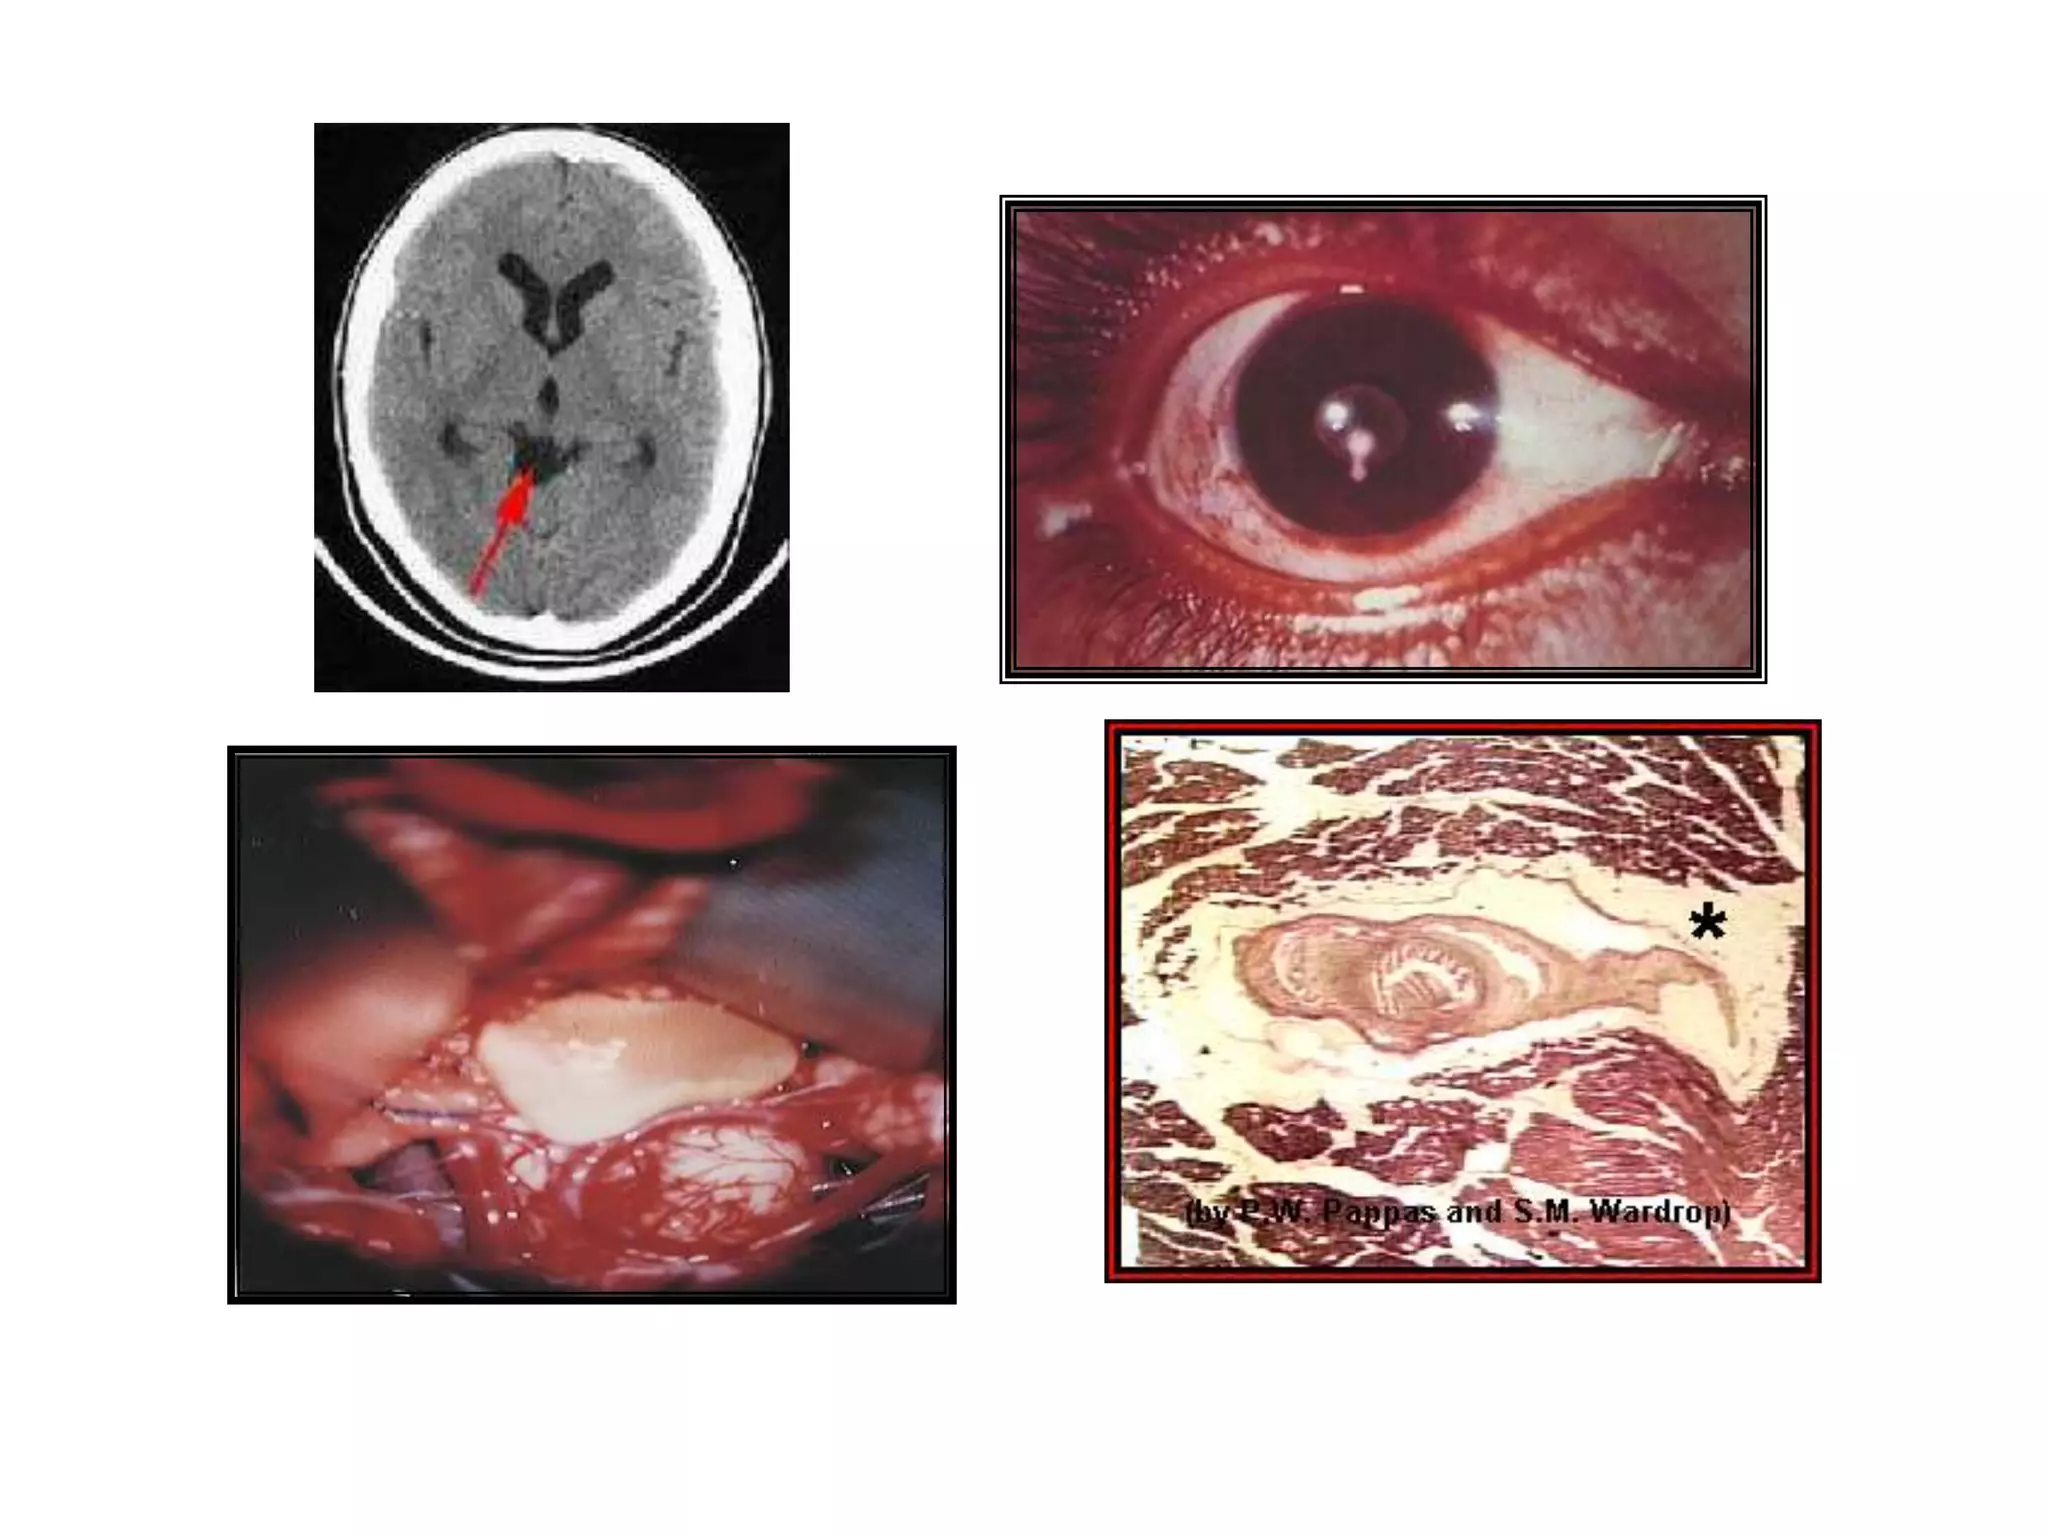

TAENIA SOLIUM2 – 7 mts x 1.5 cmsArmada (22-32 ganchos, en 2 coronas)Proglotides mas largos que anchosÚtero en forma de saculaciones con 7 a 12 ramas a cada ladoHuevos típicos

HUESPEDES DEFINITIVOS:HombreLOCALIZACION:Intestino delgadoHUESPED INTERMEDIARIO:Cerdos domésticos y salvajes, Ocasional/ hombre.NOMBRE DE LA LARVA:Cisticercus cellulosaeLOCALIZACION DE LA LARVA:	Tejido muscular, nervioso y diversos órganos

CISTICERCOSISPORCINA

Hacinamiento.DESARROLLO DE CISTICERCOSLos cerdos jóvenes son más susceptibles a la infección que los adultos (Metacéstodos mas viables en encéfalo)Cisticercus alcanza en 20 días el tamaño de la cabeza de un alfiler. (esbozo de escólex)

40 días aumenta 4 veces su tamaño (cabeza desprovista de ganchos).

60 días tamaño de un fríjol (ventosas y ganchos)

3 meses alcanza el desarrollo completoSignos - LesionesSíntomas:

Músculos de color pálido, gris-rojizo, blandos, húmedos y con variado número de cisticercos.

Vesículas compactas del tamaño y aspecto de grano de arroz, con liquido acuoso en su interior y en el centro un punto blanco opaco.

Principales sitios de localización de cisticercos:

Capas musculares profundas

Cabeza, especialmente maseteros; cuello; diafragma.

Músculos Intercostales; lengua; pierna (M. Femorales y glúteos).Viabilidad del cisticercos Se destruyen a Temperatura de 49°C.